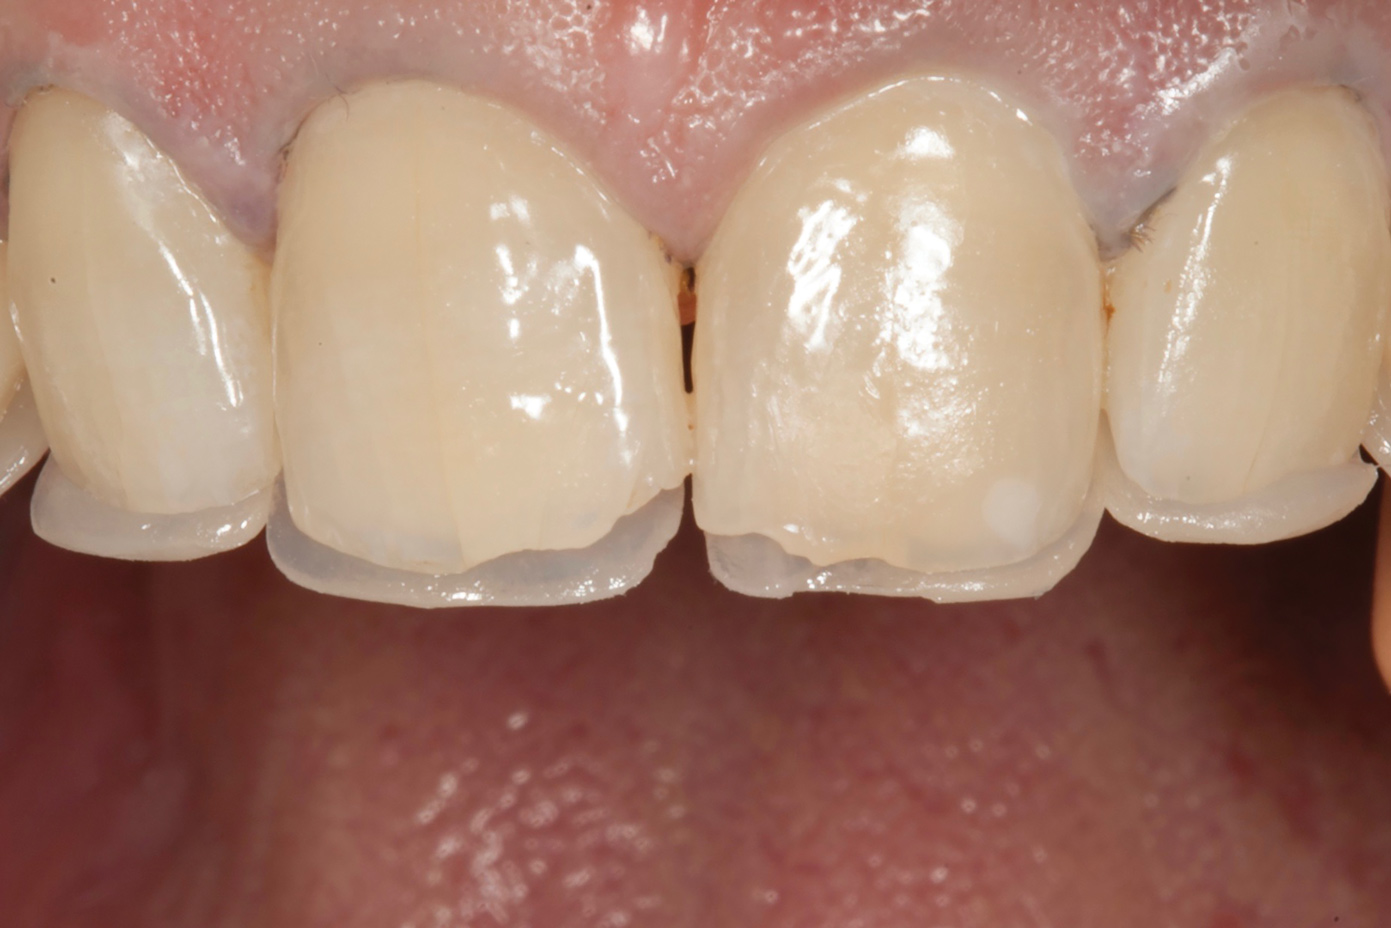

Fig 7. Lingual matrix in place.

Figure 7

Fig 8. Lingual shelf after brief curing.

Figure 8

Fig 9. Creation of dentin and enamel effects.

Figure 9

Following caries treatment and tooth preparation (Figure 6), teeth Nos. 4 through 13 were restored with direct composite veneers in stages (Figure 7 through Figure 9). Using a hybrid composite for the lingual shelf and dentin layer provides wear resistance and strength for the restoration.14,15 (The lowest wear rates for restorations and the opposing dentition occur with metal alloys, machined ceramics, and microfilled hybrid resin composites. Any adjusted and unpolished porcelain surface would elicit the most wear on the opposing teeth.11)After the composite veneers were finalized, a monolithic lithium disilicate crown was placed on tooth No. 12 during a subsequent appointment, and occlusal equilibration was carried out. Final photographs were taken a couple of weeks later (Figure 10 through Figure 14).